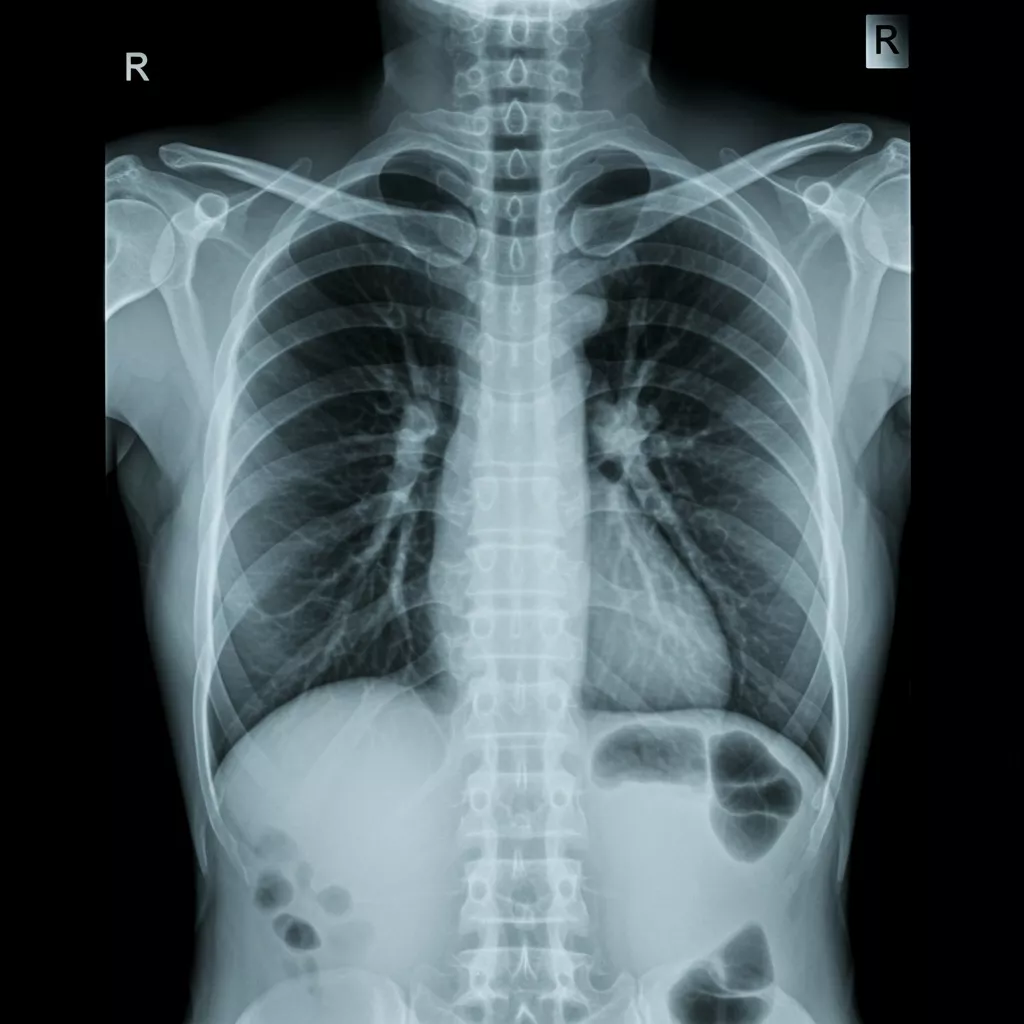

Normal Chest X-Ray: Key Features

A normal chest X-ray includes several hallmark characteristics demonstrating healthy thoracic anatomy. Some of the most important features include:

1. Clear, Symmetric Lung Fields

- Lungs appear radiolucent (dark) with normal vascular markings.

- No areas of consolidation, mass effect, or interstitial thickening.

2. Normal Heart Size and Contours

- Cardiothoracic ratio is within normal limits (typically <50% on PA view).

- Heart borders are sharp and well-defined.

3. Proper Mediastinal Width

- Trachea is midline.

- Mediastinum appears appropriately sized without widening or displacement.

4. No Pleural Abnormalities

- No visible fluid, air, or pleural thickening.

- Costophrenic angles are sharp and unobstructed.

5. Normal Bones and Soft Tissues

- Ribs, clavicles, and spine show no fractures or lesions.

- Soft tissues appear symmetric without masses or subcutaneous emphysema.

Recognizing these baseline findings provides the foundation for detecting abnormalities quickly and accurately.